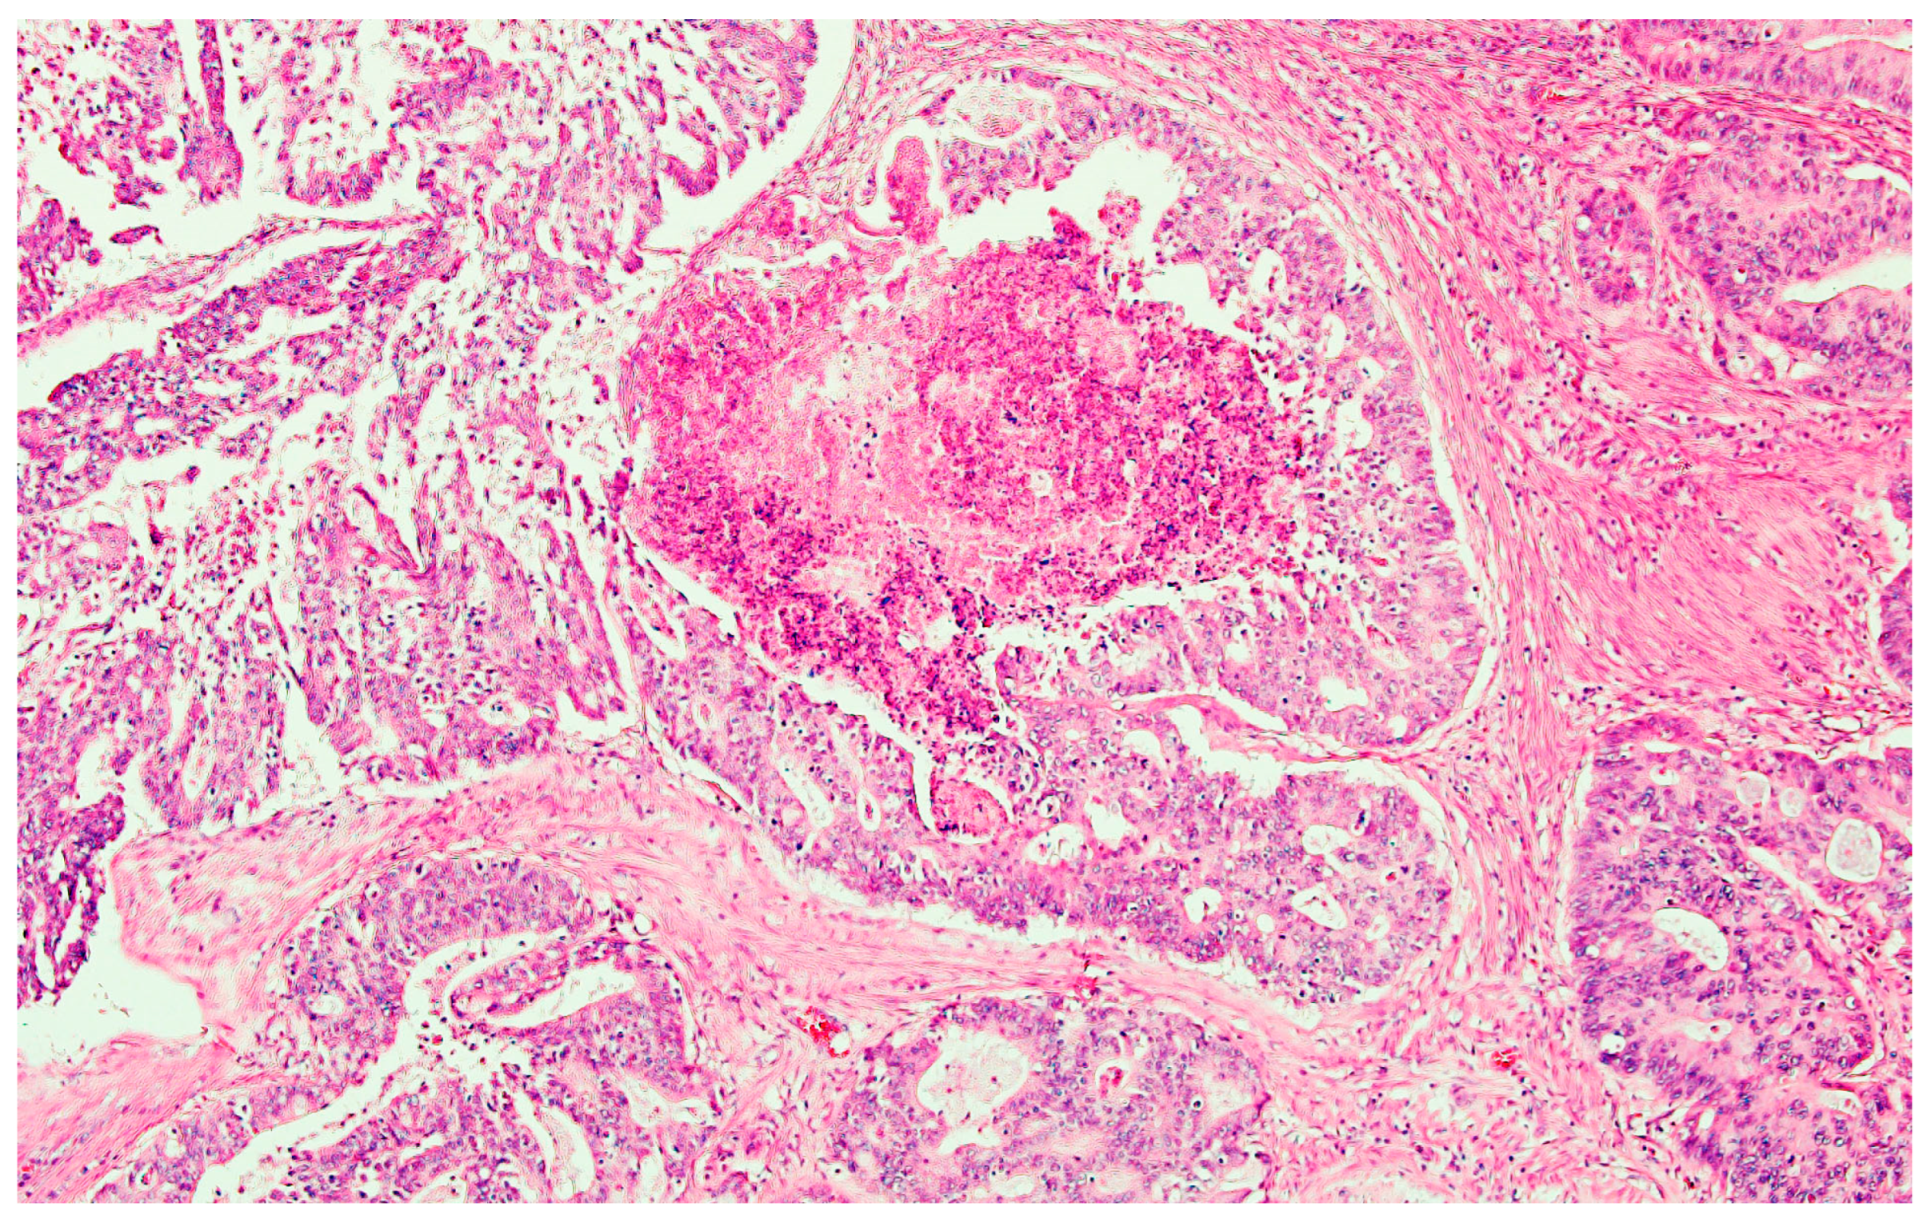

2.1. Case Report